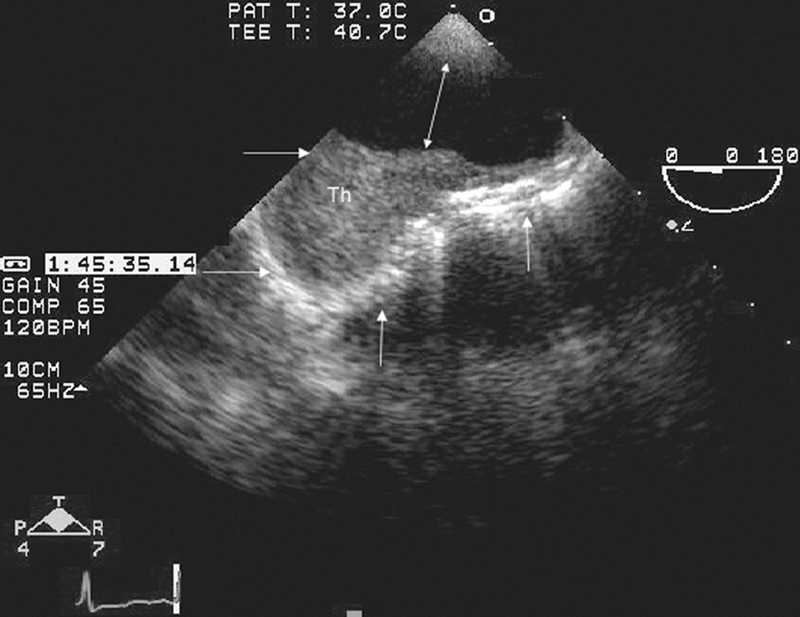

فحوصات تشخيصية لبعض امراض القلب والشرايين التاجية